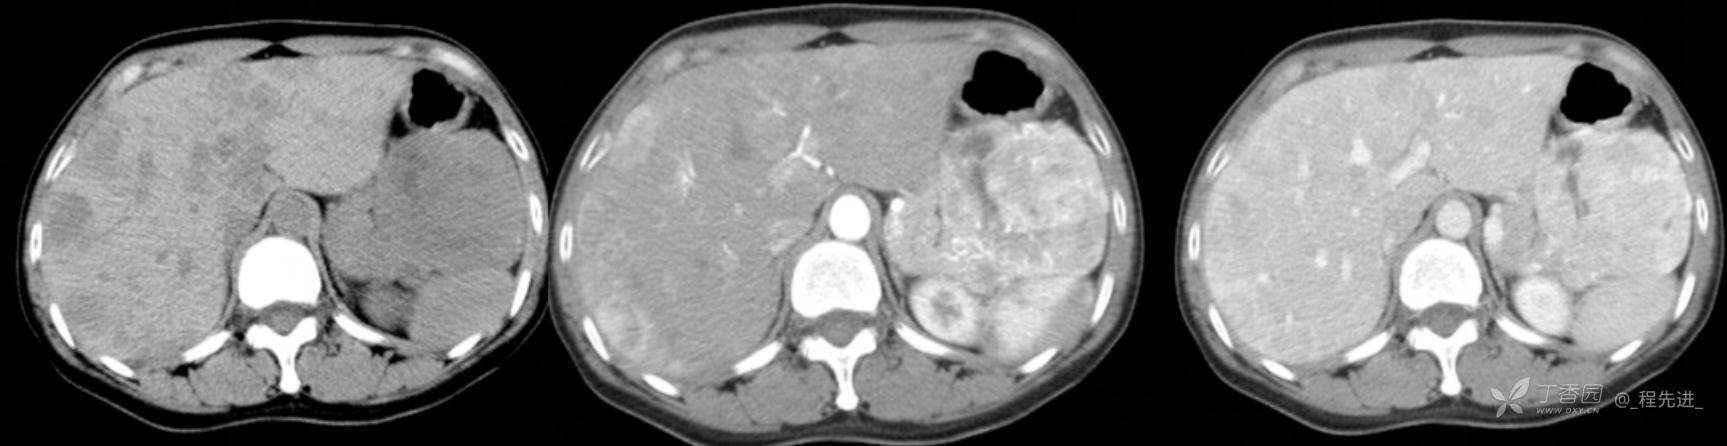

图像左边为平扫,中间的是动脉期,右边的是静脉期